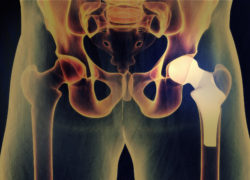

DePuy Zimmer hip replacement hip implantYou could be eligible for part of a DePuy hip implant settlement if your implant has failed and you have needed revision surgery since March 2015.

Johnson & Johnson has faced thousands of lawsuits since the FDA announced the DePuy voluntary recall of their ASR hip implant system in August 2010.

DePuy Hip Implant Settlement Due to Metal Device Issues

The DePuy hip implant settlement is available to patients who could have experienced a variety of issues from the metal-on-metal device.